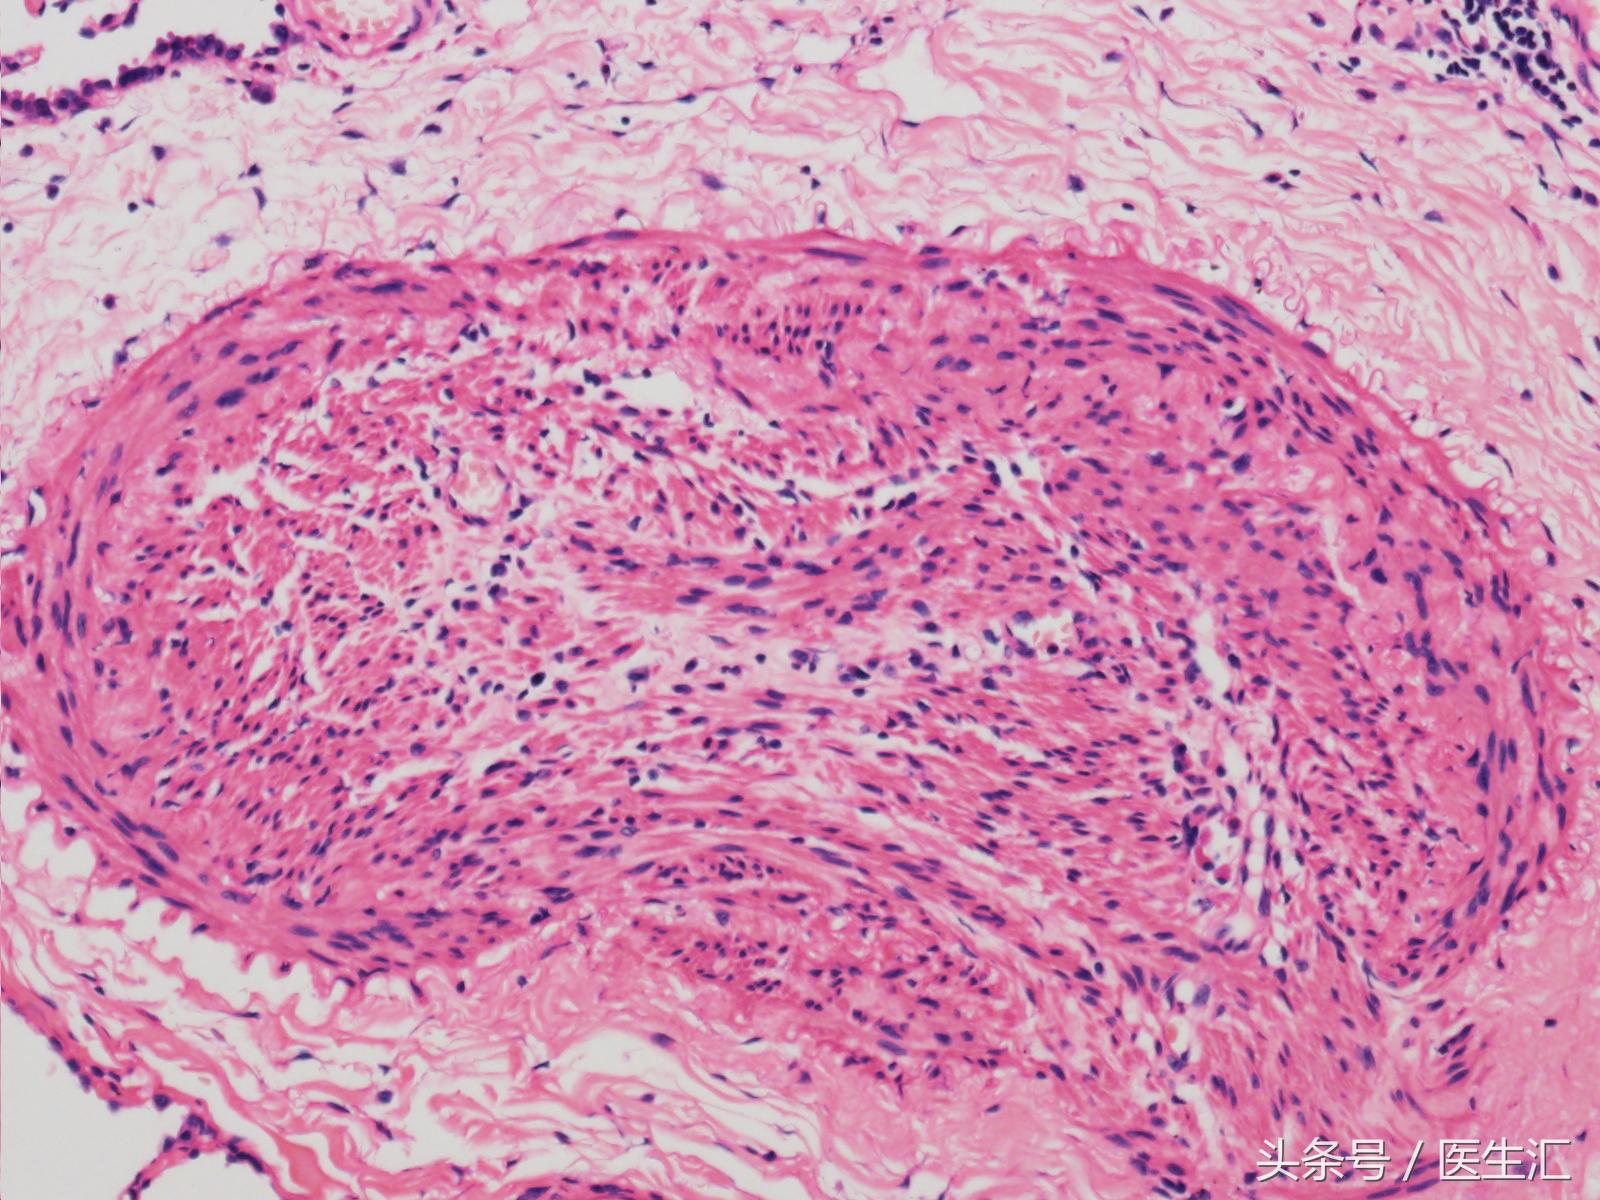

其后送病理检查,示:

结果如下:

根据结果可以看出,因为患者血管壁整体增厚,血管管腔狭窄,所以出现在肺里必定会引起肺动脉高压的表现,因为血管窄,所以肺血管的阻力是大大增加的。